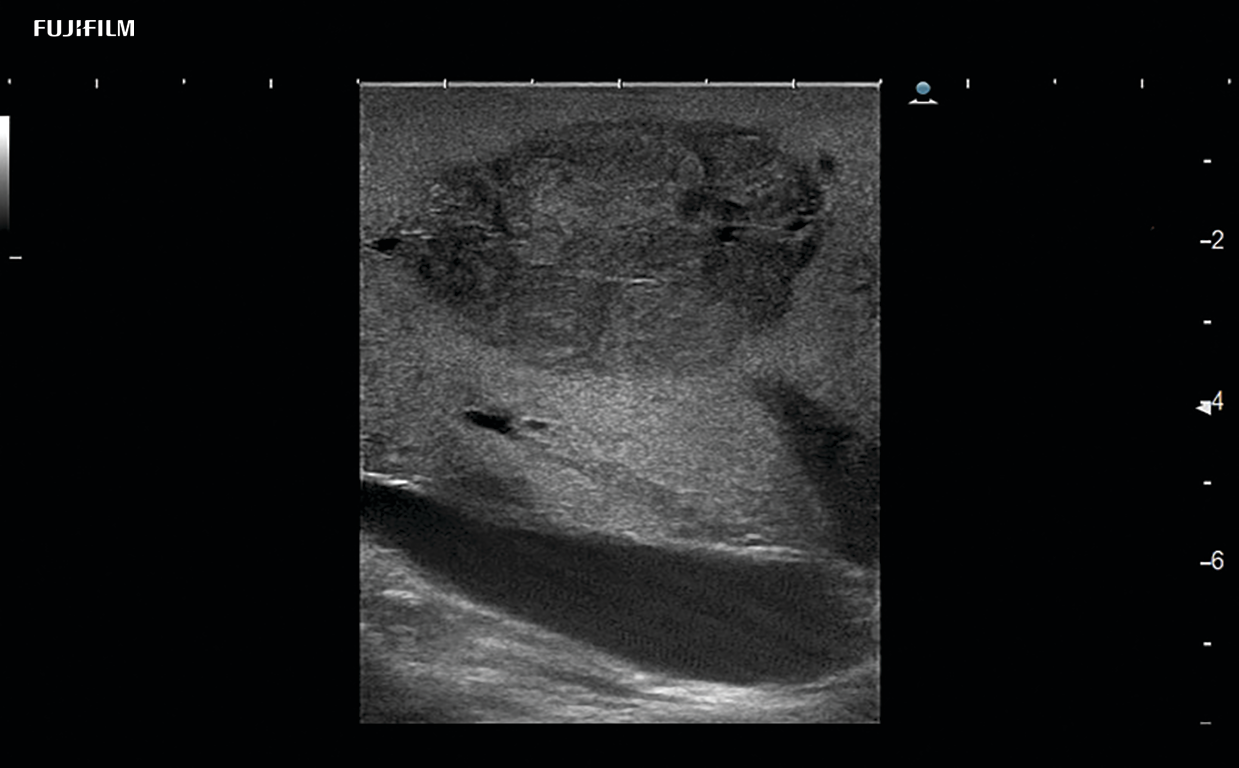

Liver Ablation Procedure using L44K

Linear array side-fire “T” transducer for open surgical procedures, providing exceptional near and far-field resolution.